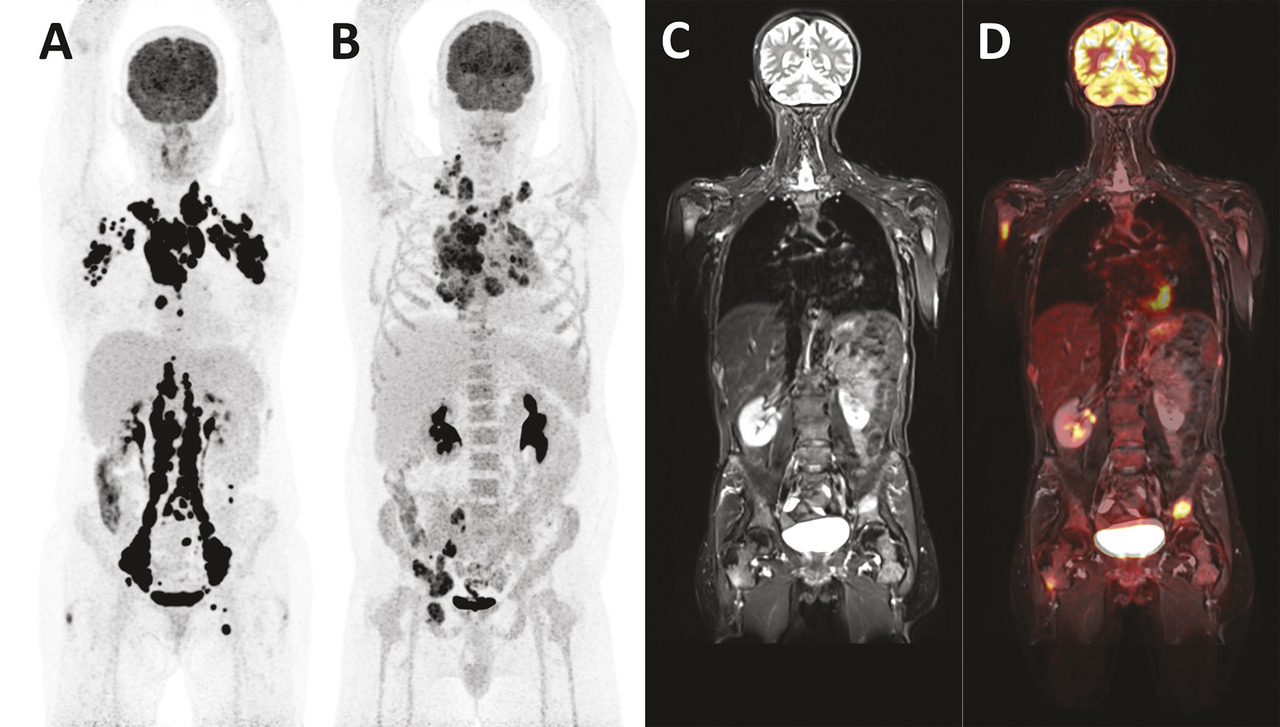

L’imagerie est réalisée à 60 ± 10 minutes après l’injection du produit radiopharmaceutique et couvre un champ d’exploration allant du haut du crâne à mi-cuisse, parfois jusqu’aux pieds. Le respect strict de certaines précautions telles que le jeûne préalable d’au moins 4 heures, le contrôle de la glycémie, qui doit être inférieure ou égale à 7 mmol/L (ou ≤ 11 mmol/L en cas de diabète), le repos strict sans stimulation musculaire pendant l’heure de captation, assure la possibilité d’interpréter correctement l’examen et une reproductibilité de l’analyse quantitative du métabolisme. L’enregistrement des images dure 15 à 20 minutes. Les tissus normaux captent très peu le 18F-FDG, à l’exception du cerveau (consommateur de glucose), du myocarde (switch métabolique vers les acides gras en cas de jeûne) et des voies urinaires (élimination du radiotraceur). En conséquence, les lésions tumorales sont visibles, avec un très fort rapport signal/bruit (v. figure ). La consommation de glucose des tumeurs peut être mesurée par le calcul de la standardized uptake value (SUV), un indice semi-quantitatif qui reflète l’activité de la prolifération tumorale par rapport à une distribution homogène du traceur dans l’organisme.

Dans les lymphomes, la TEP-TDM au 18F-FDG est recommandée lors du bilan d’extension initial des lymphomes de Hodgkin et des lymphomes non hodgkiniens, habituellement avides (v . figure ). Elle permet de réaliser un inventaire des lésions ganglionnaires et extraganglionnaires pour la stadification (et dans certains cas de se passer de la biopsie ostéomédullaire systématique), de mesurer le volume métabolique tumoral, d’identifier les éventuelles composantes de bas grade (SUV < 10) et de haut grade (SUV > 10) pour guider la biopsie, et enfin de disposer d’un examen de référence pour évaluer ensuite la réponse au traitement. L’évaluation thérapeutique s’appuie sur l’utilisation consensuelle de l’échelle de Deauville 2009 (tableau 1 ), qui compare visuellement l’intensité d’un foyer résiduel avec des organes de référence, comme le médiastin et le foie. La réponse au traitement est ensuite exprimée selon la classification de Lugano 2014 (tableau 2 ) en quatre catégories : réponse métabolique complète (RMC), réponse partielle (RMP), maladie métaboliquement stable (MMS) ou maladie métaboliquement progressive (MMP).2 Dans le lymphome diffus à grandes cellules B, l’évaluation précoce de la réponse après les deux premières cures de chimiothérapie a une forte valeur pronostique et peut s’appuyer sur le calcul du pourcentage de réduction du SUV entre l’imagerie préthérapeutique et l’imagerie précoce (ΔSUV), rendant plus objective l’interprétation. Le seuil au-delà duquel un patient est considéré en bonne réponse après deux cures est fixé à ΔSUV > 66 %.

Dans les myélomes, l’IRM et la TEP permettent de caractériser la prolifération ostéomédullaire (lésions focales, infiltration diffuse) bien mieux que les radiographies standard et font partie intégrante de la nouvelle stadification de Salmon et Durie « plus ».3 Ces modalités d’imagerie peuvent également mettre en évidence des atteintes extramédullaires de la maladie, et peuvent être réalisées simultanément sur les machines hybrides TEP-IRM (v . figure ). L’IRM est beaucoup plus sensible pour détecter l’infiltration diffuse, corrélée au pourcentage de plasmocytes présents dans la moelle osseuse, et la TEP permet de caractériser l’agressivité des lésions focales. Ainsi, le véritable intérêt de l’imagerie métabolique dans l’évaluation initiale des myélomes est pronostique, en particulier avant autogreffe de cellules souches : la présence d’au moins trois lésions hypermétaboliques et/ou d’une atteinte extramédullaire sont des facteurs de mauvais pronostic. Un SUV > 4,2 a également été décrit comme étant un facteur péjoratif, mais son utilisation est plus controversée. Enfin, les deux modalités sont indiquées pour l’évaluation de la réponse thérapeutique, la TEP étant plus précoce que l’IRM : la disparition de tout hypermétabolisme lésionnel après traitement permet d’identifier les patients sans maladie résiduelle minime qui auront une meilleure survie sans progression.